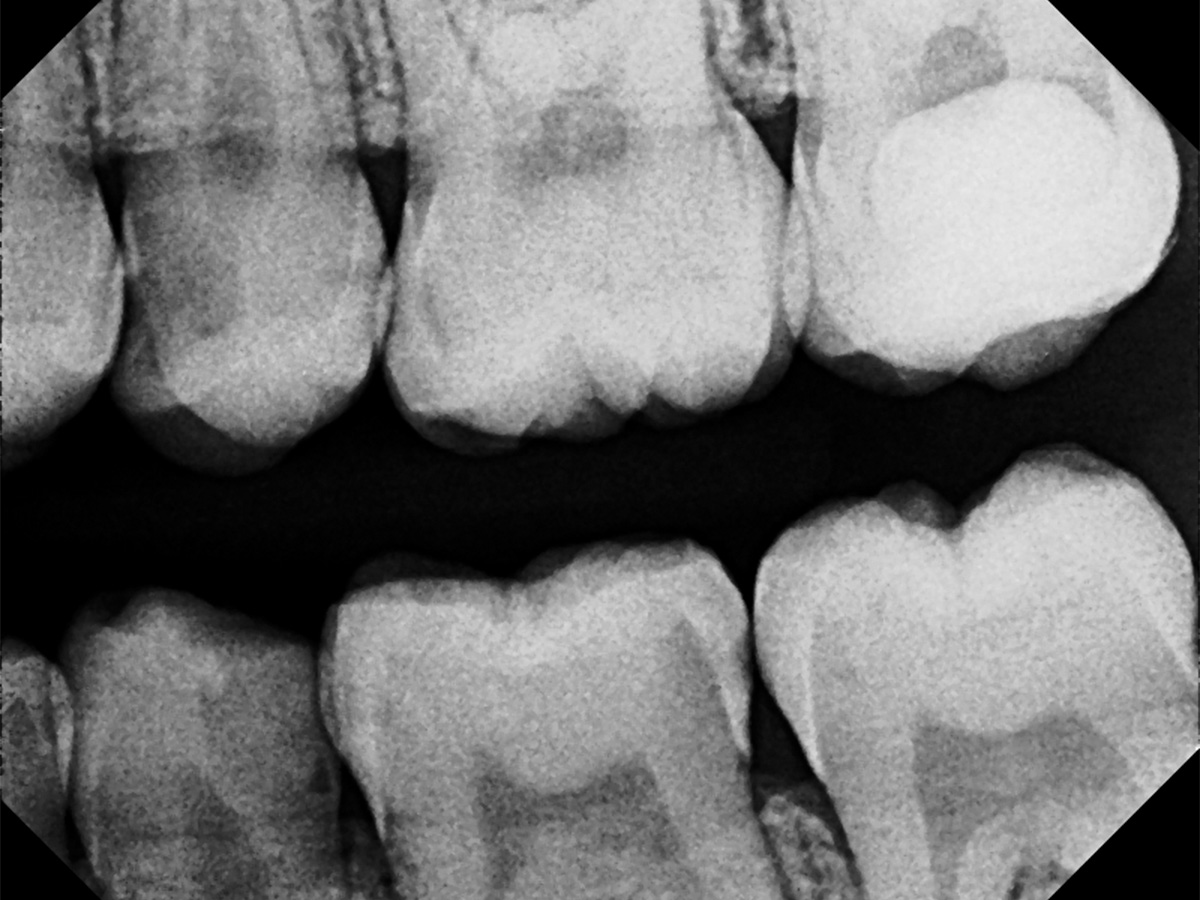

Abbildung 14

Recall: Aufnahme des Zahnes 25 fünf Monate nach Kappung.